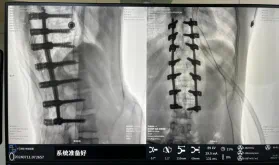

圖為置釘后

據(jù)悉脊柱側(cè)彎手術(shù)治療后可以保持軀干平衡,改善外觀并防止畸形進(jìn)一步發(fā)展?;颊叩纳钯|(zhì)量得到提高,進(jìn)而減少脊柱過度畸形可能帶來的疾病的發(fā)生率,外觀上的積極變化往往也能帶來患者心理與精神的積極變化。臨床上會綜合考慮患者的年齡、側(cè)彎程度、進(jìn)展趨勢、骨質(zhì)條件、鄰近節(jié)段情況、手術(shù)節(jié)段等因素,合理采用個性化的手術(shù)方式進(jìn)行治療。然而,由于脊柱神經(jīng)血管密布,手術(shù)操作相對復(fù)雜,手術(shù)難度高、風(fēng)險大,傳統(tǒng)脊柱側(cè)彎的手術(shù)方式往往有較高的神經(jīng)或脊髓損傷風(fēng)險。故此次科室決定開展機(jī)器人輔助導(dǎo)航下脊柱側(cè)彎矯形、植骨融合內(nèi)固定手術(shù)。術(shù)前,醫(yī)生團(tuán)隊在機(jī)器人多維度圖像融合智能手術(shù)規(guī)劃功能的輔助下,預(yù)先規(guī)劃了理想的置釘路徑。術(shù)中,天璣骨科手術(shù)機(jī)器人準(zhǔn)確遵循術(shù)前規(guī)劃,根據(jù)配準(zhǔn)結(jié)果,實時定位并準(zhǔn)確執(zhí)行置釘操作,所有導(dǎo)針均用電鉆置入,一次性成功,協(xié)助醫(yī)生順利完成手術(shù)。最終,在麻醉科、手術(shù)室密切配合下,歷時3小時成功完成側(cè)彎矯形術(shù),出血量僅500ml。術(shù)后,患者恢復(fù)良好,大小便及下肢神經(jīng)運動感覺正常。

此次在充分保證患者安全和手術(shù)效果的前提下使用機(jī)器人輔助下手術(shù)的成功實施,大大降低了高難度手術(shù)的風(fēng)險,并進(jìn)一步減輕了患者手術(shù)創(chuàng)傷、縮短了康復(fù)時間。這也標(biāo)志著南方醫(yī)院贛州醫(yī)院脊柱外科治療個性化、精準(zhǔn)化、智能化水平進(jìn)一步提升。